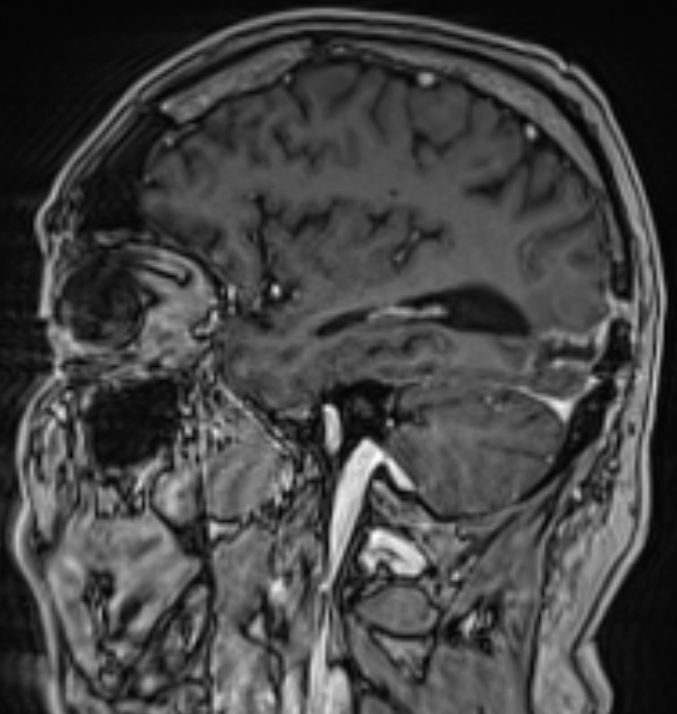

• 54-jähriger Mann, der vor 4 Jahren ein Adenokarzinom des rechten Lungenoberlappens cT4 cN1 M0 entwickelte

•  Cisplatin / Alimta - Chemotherapie, dann Radio –Chemotherapie 50Gy, 3 Zyklen simultan Cisplatin und Pemetrexed

• extrapleurale Oberlappenresektion,  Lymphadenektomie

• postoperatives Stadium ypT3 ypN0 L0 V0 G3

• adjuvante Bestrahlung der Thoraxwand rechts ED 3 Gy, GD 30 Gy

• vor 2 Jahren Metastase links parieto – occipital,  neurochirurgische Entfernung, Bestrahlung des Neurokraniums mit 30 Gy, ED 3 Gy

• vor 1 Jahr  Exstirpation einer Hirnmetaste links occipital, Bestrahlung des Hirnmetastasenbettes links occipital mit 40 Gy, ED 2 Gy

Die linke Spalte zeigt MRTs vor 7 Monaten, die rechte Spalte aktuelle MRTs.

Die MRTs zeigen eine Zunahme der Gadolinium-anreichernden Bezirke. Die Exzision erbrachte Großhirngewebe mit Anteilen einer Nekrose. Kein Tumorgewebe.